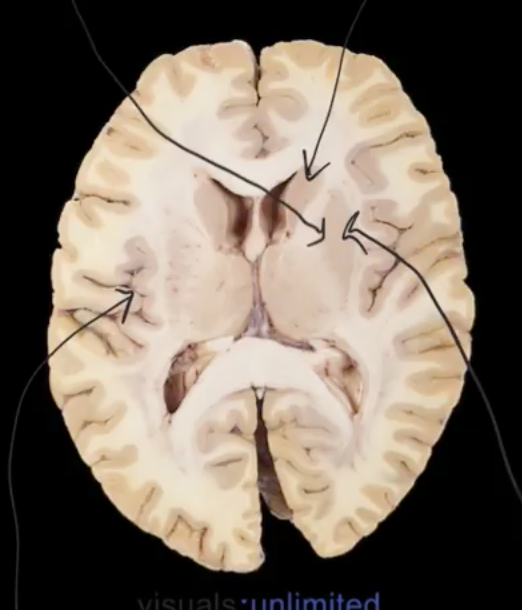

label

what structres r deep to the insula?

putamen and globus pallidus, caudate nucleus

part of basal ganglia